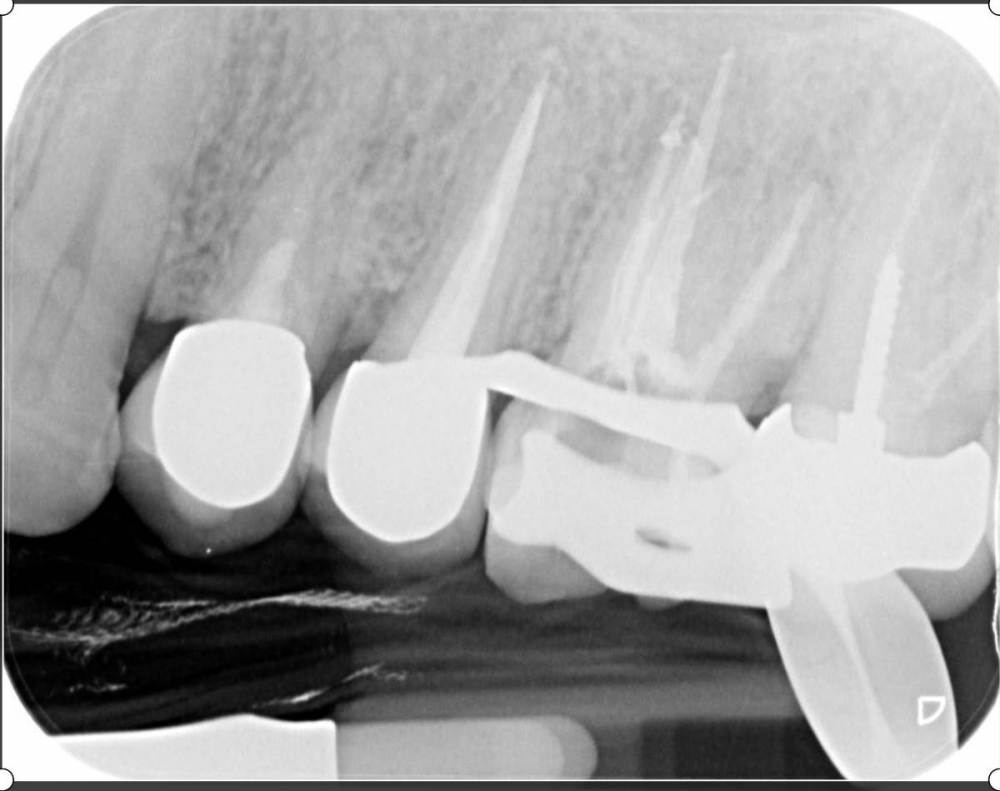

lola-1234 Опубликовано 12 августа, 2021 Автор Поделиться Опубликовано 12 августа, 2021 (изменено) Я прям заморочилась, нашла снимок 2017 года. И эта штука в зубе уже была. Но к счастью, больше камень не стал за это время. Изменено 12 августа, 2021 пользователем lola-1234 Ссылка на комментарий

annda Опубликовано 13 августа, 2021 Поделиться Опубликовано 13 августа, 2021 (изменено) Если честно, глядя на снимок, на фото зуба( на его цвет) , ваши жалобы и ваш анамнез( то , что вы сказали про травму), я вообще сомневаюсь , что клык был живой к моменту имплантации. Скорее всего, там уже был периодонтит,то есть мертвый он давно и безнадежно. А операция, манипуляции рядом с ним( удаление, сверление, установка имплантата) просто спровоцировали обострение хронического периодонтита в клыке, вот и все. Цвет одного клыка и другого, с противоположной стороны, одинаковый? Изменено 13 августа, 2021 пользователем annda Ссылка на комментарий

lola-1234 Опубликовано 28 октября, 2021 Автор Поделиться Опубликовано 28 октября, 2021 (изменено) Снова пишу вам на форум. Уже не знаю,что делать. Рассказываю. Установили мне формирователи, импланты оба прижились. А вот моя проблемма никуда не делась ? Зуб так и болит, причём дергающая боль по ощущением там где заканчивается кончик корня. На зуб укусить не возможно, больно. Мой хирург не верит, что болит из-за импланта. Говорит,что стоит хорошо, далеко от зуба. Имплант прижился, значит инфекции нет. Кстати как оказалось, зуб ещё живой. Мне опять его протестировали на холод. Видимо я тогда рано запаниковала. Но на снимке возле корня уже видно затемнение. Но что вызвало его воспаление не понятно. Мне врач предлагает удалять нерв. А там посмотрим. Если будет болеть дальше, то тогда выкручивать уже имплант придётся. А если мы выкрутим сначала имплант, а зуб так и будет болеть, то это худший сценарий. А мне так жалко клык. Он же тогда мертвый станет. ? Так и живу с болью, не решаюсь зуб депульпировать. Никто из врачей мне точно не может сказать что делать. Похоже ситуация не стандартная, и врачи сами не знают в чём причина. Изменено 28 октября, 2021 пользователем lola-1234 Ссылка на комментарий